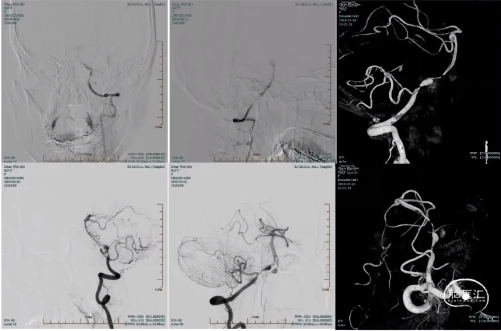

术中DSA:

双支架(Enterprise4.5/37mm+LVIS45/30mm)双微管技术+弹簧圈进行载瘤动脉血流重建

6个月后DSA

患者术后症状明显减轻并逐渐完全消失,6个月DSA可见载瘤动脉血流重建良好。